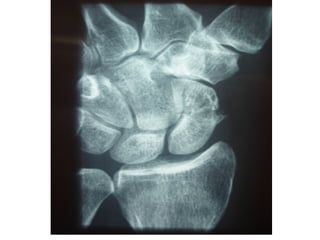

IMAGING

XRAYS: 4 essential views

PA view

Lateral view identify majority

Supinated oblique of fractures

Pronated oblique

SCAPHOID VIEW: is a PA radiograph with the wrist

extended 30° and deviated ulnarly 20°. This view helps to

stretch out the scaphoid and is also used for assessing the

degree of scaphoid fracture angulation

A clenched-fist radiograph has also been useful for

visualization of the scaphoid waist.

X-RAYS

Scaphoid axis

The true axis of the scaphoid is the line through the

midpoints of its proximal and distal poles. Since the

midpoint of the proximal pole is often difficult to

appreciate, an almost parallel line can be used that is

traced along the most ventral points of the proximal

and distal poles of the bone